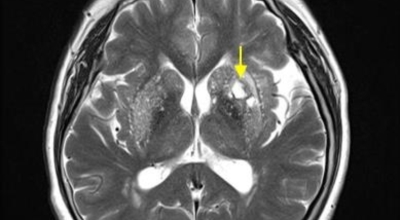

뇌경색의 경색이란 허혈성 괴사를 말해요. 여기서 허혈이란 혈관이 막히는 것을 말하고 괴사는 말 그대로 일부가 죽는 것을 말하는데 뇌경색의 경우 뇌의 혈관이 막혀 뇌세포 일부가 죽는 걸 의미해요. 뇌혈관이 막혔다 해서 혈액 공급이 안되는것은 또 아니에요.

막힌 혈관으로도 혈액이 공급되긴 하나 혈관이 막혀있어 혈액을 보내긴 하나 제대로 흐르지 못하고 혈액이 쌓이고 축적되어 물풍선에 물이 꽉 차서 터지듯 뇌혈관이 터지는 경우가 일어날 수 있는데 이를 뇌출혈 이라고 해요. 물론 외상으로 인한 뇌출혈도 있지만 이처럼 뇌경색으로 인해 혈관이 막혀 터지는 경우도 있어요.